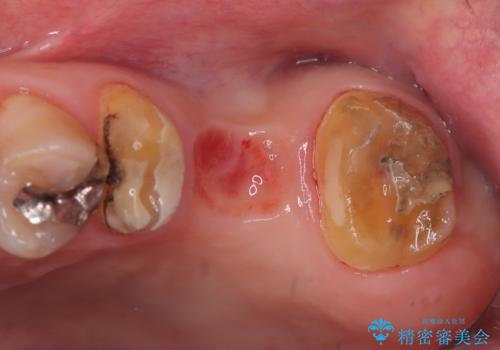

保険適用のメタルインレーを除去したところ、ポンティック部の過度な加圧によって歯肉が強く発赤していたため、一度仮歯に置き換え歯肉の治りを待った後、適切な加圧強さのオールセラミッククラウンブリッジをセットしています。